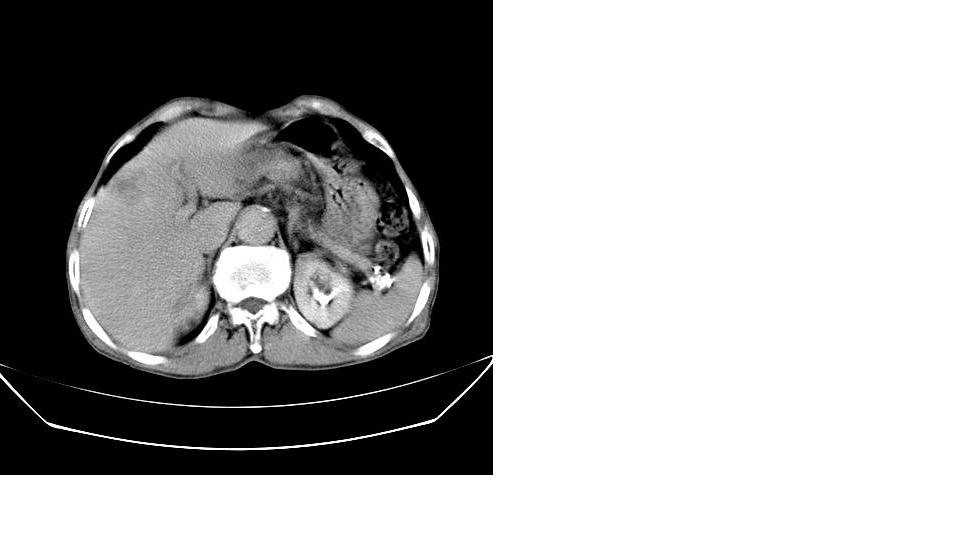

男,76岁,上腹部疼二天来就诊,彩超提示肝左叶占位,随后做上腹部ct平扫,今天做上腹部ct增强扫描,手工推药,效果不好,请谅解。

肝左叶s4肿块强化形式大概是:慢进慢出,逐渐强化----考虑血管瘤/腺瘤?{动脉期应更提前扫}。

肝右叶前段hcc

1)肝右叶前段低密度灶,不排除肝癌可能;建议查afp。2)右肾上极囊肿。

肝内胆管积气扩张,胆囊增大,肝右前叶低密度灶,逐渐强化,一元论,胆系感染,局限性肝脓肿;右肾囊肿。

考虑肝s4段肝脓肿可能?未排除肝癌。右肾上极囊肿。